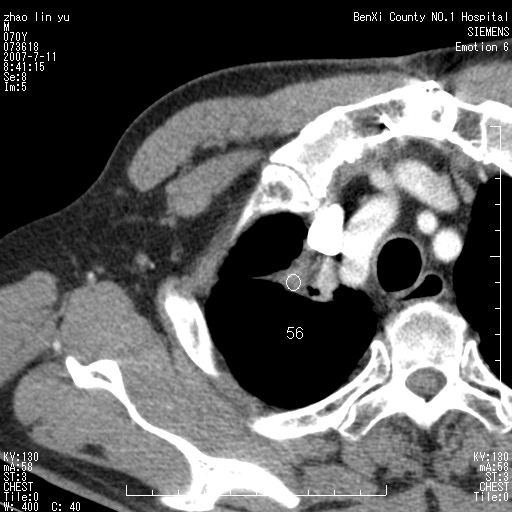

以下是引用王靖旗在2007-7-10 17:12:00的发言:[br] 男、70、咳嗽两个月,半年前换瓣手术,胸片未见异常,于昨天行x片发现右肺上野大片影,行ct扫描,这里是减薄图像,余肺正常。明天晚上会有增强扫描片,到时我会上传。[br][br] 冠状位请大家细看,应该是有意义的,[br][br] 请大家先看平扫发表意见。[br][br]

以下是引用zhangzhongshou在2007-7-10 21:43:00的发言:[br]右肺上叶周围型肺癌,以孤立型细支气管肺泡癌可能性大。